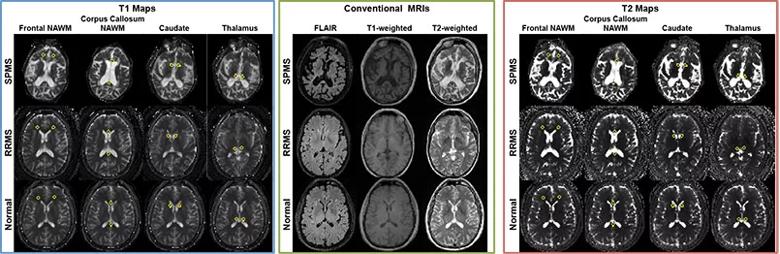

At the 2016 annual meetings of the American Academy of Neurology and the International Society for Magnetic Resonance in Medicine, our research team presented results from the first MRF study applied in patients with MS.3 We conducted a cross-sectional study to investigate whether MRF detects differences in normal-appearing white matter (NAWM) and normal-appearing gray matter (NAGM) between MS subjects and healthy controls as well as between patients with relapsing-remitting (RR) and secondary progressive (SP) MS (Figure 1). We also sought to understand the clinical relevance of MRF by measuring correlation of MRF findings with clinical disability.

Figure 1. MRF-based T1 maps (left), conventional MRIs (middle) and MRF-based T2 maps (right) from patients with secondary progressive MS (SPMS, top rows), patients with relapsing-remitting MS (RRMS, middle rows) and healthy controls (bottom rows).

The study’s key results included the following:

• Between healthy controls and the MS groups, T1 values in the thalamus and caudate were significantly different (both P < .01).

• Between patients with RRMS and those with SPMS, T1 values in frontal NAWM were significantly different, as were T1 and T2 values in T2 lesions (all P ≤ .001).

• T1 values in frontal NAWM showed the highest correlation with both the Expanded Disability Status Scale (EDSS) and the MS Functional Composite (MSFC) scores (absolute Spearman rank correlation > 0.61), as detailed in Figure 2.

• T1 and T2 values in T2 lesions also correlated with MSFC score (Spearman rank correlation = –0.679 and –0.582 respectively, P < .001).

Our findings show that MRF provides simultaneously acquired and intrinsically registered maps of multiple relaxation parameters. In agreement with previous T1-mapping techniques, we also found increased T1 in normal-appearing structures. T2 was increased in certain normal-appearing regions, similar to prior evidence that showed changes in NAWM but not in deep gray matter structures.

In addition to demonstrating differences between healthy controls and patients with MS, MRF distinguished the clinical course of disease even in this small sample size. This indicates a high sensitivity for detecting underlying nonlesional changes in MS and suggests that MRF may provide a window into the pathophysiology of the disease. Significant correlations with the MSFC and EDSS scores likewise suggest that MRF measures capture a clinically meaningful change in normal-appearing tissue.